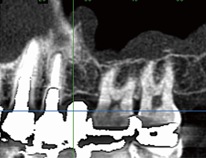

1. 正確に骨質を把握

他の歯科用CTは歯や顎の骨を立体的に把握することはできるものの、骨質(硬さ)について正確に把握することはできません。

一方で、当院の歯科用CTは骨質(硬さ)を正確に計測できるため、骨質(硬さ)を事前に把握しておくことが重要であるインプラント治療に特に有効です。当院の歯科用CTは数ある歯科用CTの中でも特に優れた性能を持つ装置です。